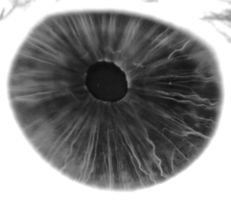

في البشر ومعظم الثدييات والطيور، القزحية ( Iris ؛ الجمع: قزحيات أو قزحية العين) عبارة عن هيكل حلقي رقيقة في العين ، المسؤولة عن السيطرة على قطر وحجم الحدقة وبالتالي كمية الضوء الوصول إلى شبكية العين . يتم تحديد لون العين من خلال القزحية. من الناحية البصرية ، البؤبؤ هو فتحة العين ، بينما القزحية هي الحجاب الحاجز .

القزحية تتكون من طبقتين: الطبقة الصبغية الليفية الوعائية الامامية المعروفة باسم سدى ، وتحت سدى خلايا الظهارية المصطبغة.

ترتبط السدى بالعضلة العاصرة ( العضلة العاصرة الحدقة )، والتي تنقبض الحدقة بحركة دائرية ، ومجموعة من العضلات الموسعة ( الحدقات الموسعة ) التي تسحب القزحية بشكل شعاعي لتكبير الحدقة وتسحبها في ثنايا.

تنقسم القزحية إلى منطقتين رئيسيتين:

- المنطقة الحدقة pupillary zone هي المنطقة الداخلية التي تشكل حافتها حدود الحدقة.

- المنطقة الهدبية ciliary zone هي بقية القزحية التي تمتد إلى أصلها في الجسم الهدبي.

الطويق collarette هو أسمك منطقة في القزحية، تفصل الجزء الحدقي عن الجزء الهدبي. الطويق هي بقايا طلاء الحدقة الجنيني..[1] يتم تعريفه عادةً على أنه المنطقة التي تتداخل فيها العضلة العاصرة مع العضلة الموسعة. تمتد الحواف الشعاعية من المحيط إلى منطقة الحدقة ، لتزويد القزحية بالأوعية الدموية. جذر القزحية هو أنحف واكثر طرفية.[2]